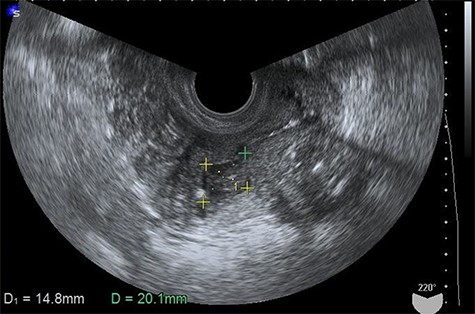

A 67-year-old postmenopausal woman, gravida 0, presented with purulent discharge and abdominal distension. Her past medical, surgical, gynecological and family histories were all unremarkable. The vaginal examination showed a foul smelling, green vaginal discharge and no tenderness of the uterus. Vaginal swab cultures grew Escherichia coli. The endometrial Papanicolaou test was negative. Laboratory results, including the blood count, differential, liver function and renal function, were within the normal range. There was no fever, weight loss or palpable lymphadenopathy and organomegaly. The transvaginal ultrasound image showed the presence of hypoechoic fluid in the uterine cavity, compatible with a diagnosis of pyometra (Fig. 1). Drainage of the purulent contents by uterine Foley catheter insertion was performed. The culture of the pus grew Klebsiella pneumoniae and E. coli. After draining the fluid, her symptoms disappeared temporarily. However, 3 months later, she was admitted to our hospital with abdominal pain that gradually worsened. On physical examination, her abdomen was very tender and showed diffuse peritoneal signs. Her vital signs were stable, but laboratory studies detected a mild increase in the levels of leukocytes (9510/μl) and C-reactive protein (1.24 mg/dl). The carcinoembryonic antigen (CEA) level was significantly increased (10.2 U/ml), and the cancer antigen-125 level was slightly increased at 102.7 U/ml. The magnetic resonance imaging scan demonstrated a pelvic mass involving

Transvaginal ultrasonogram showing the presence of hypoechoic fluid in the uterine cavity.